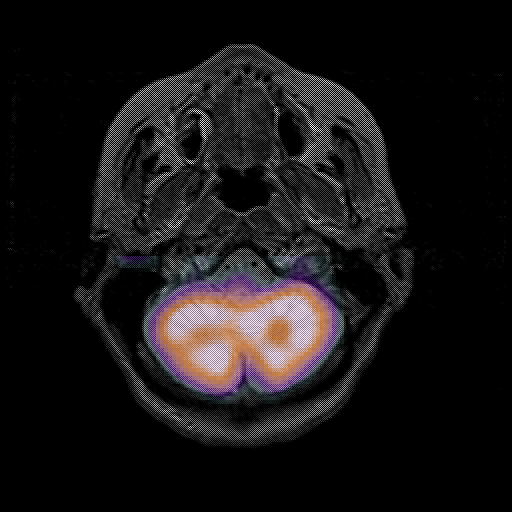

overlay : Slice 9

Slice 9

MRCBFCBF with

T1PDT2T1PDT2